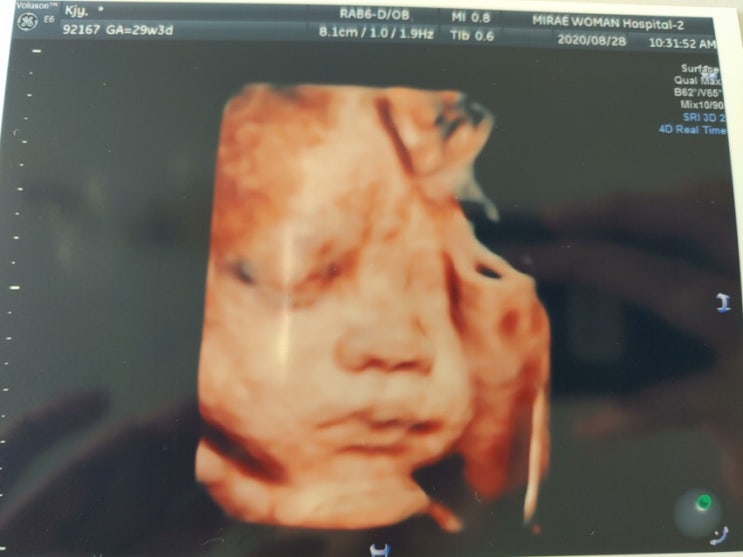

[둘째] 29주3일~37주 4일 : 입체초음파 / 아산병원 진료

8월 28일 금 / 29주 4일 지난번 아산병원 진료 이후 1달 뒤에 진료가 있어서 중간에 열무도 보고 입체 촘파...